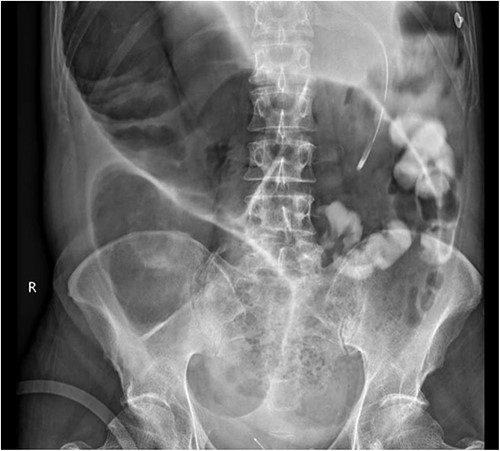

The colorectal team was consulted, and the patient received increased doses of aperients and suppositories as well as regular abdominal X-ray screening to monitor for colon dilatation. Despite this, the patient had minimal clinical improvement with ongoing abdominal bloating and pain and lack of bowel action, presenting a clinical dilemma of pseudo-obstruction, or AL with colonic involvement. A decision was made to proceed with flexible sigmoidoscopy, which found distended colon with faeces in the lumen, no mucosal changes to suggest ischaemia, and no obvious mechanical obstruction (Fig. 2).

Flexible sigmoidoscopy demonstrating distended (a) transverse and (b) descending colon with faeces in the lumen and no mucosal changes to suggest ischaemia or inflammation.